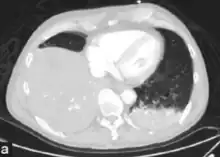

Pneumococcal antigen (cell wall C polysaccharide) may be detected in various body fluids. Older detection kits, based on latex agglutination, added little value above Gram staining and were occasionally false-positive. Better results are achieved with rapid immunochromatography, which has a sensitivity (identifies the cause) of 70–80% and >90% specificity (when positive identifies the actual cause) in pneumococcal infections. The test was initially validated on urine samples but has been applied successfully to other body fluids.[28] Chest X-rays can also be conducted to confirm inflammation though are not specific to the causative agent.[29][13]

CT pneumonia